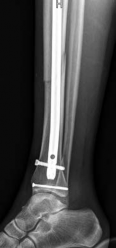

Nail Insertion and Distal Interlocking

Following meticulous preparation, the canal is reamed sequentially. Care must be taken not to over-ream the distal segment, which could compromise the already tenuous metaphyseal bone stock. The nail is inserted gently; forceful impaction is strictly avoided to prevent displacing the previously secured articular block.

Image

Distal interlocking must be maximized. The surgeon should utilize a minimum of three, and ideally four, distal locking screws, engaging the bone in multiple planes (e.g., two medial-to-lateral, one anterior-to-posterior). This multi-planar fixation is essential to control rotation and angular displacement in the wide metaphyseal bone.